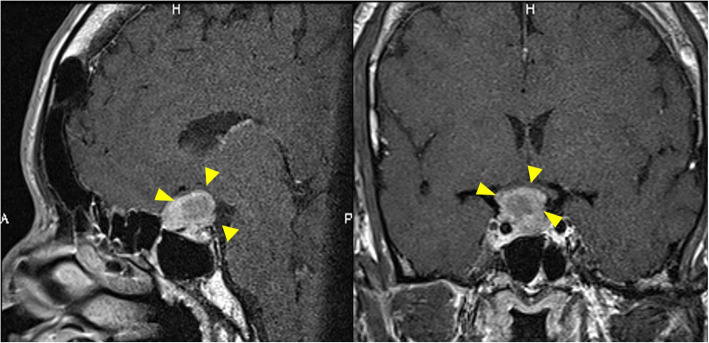

Magnetic resonance imaging (MRI) of the whole spine revealed stenosis with an intensity change in spinal cord at C6/7 and extensive spinal cord compression in the thoracic spine (Figs. 3b, d). Contrast-enhanced MRI of the brain showed a mass without contrast enhancement on the right side of the anterior pituitary gland (size, 10 mm × 12 mm × 10 mm) with suprasellar and parasailer extension; the image revealed a pituitary macroadenoma (Fig. 4).

Fig. 4.

Preoperative contrast-enhanced MRI of the brain. It showed mass without contrast effect on the right side of the anterior pituitary gland (size, 10 mm × 12 mm × 10 mm) with suprasellar and parasellar extension

The patient’s most remarkable symptom was paraplegia, and we diagnosed myelopathy due to thoracic OPLL. Furthermore, we suspected acromegaly because of the characteristic facial features and blood test findings (ALP 432 IU/L, GH 80.3 ng/ml, IGF-1914 ng/ml). Contrast-enhanced MRI of the brain performed by the endocrinology department showed a pituitary adenoma (Fig. 4). The patient’s symptoms satisfied the diagnostic criteria for acromegaly. Neurosurgery was scheduled for the pituitary adenoma, but spinal surgery was prioritized due to fear of exacerbation of neurological symptoms.